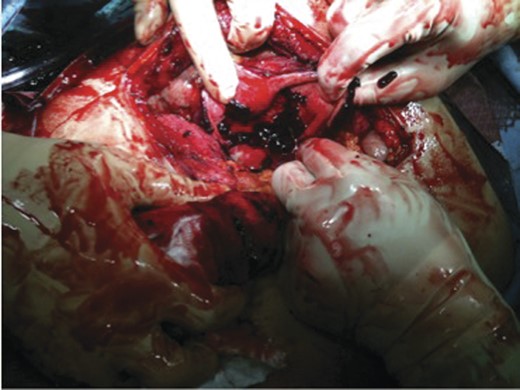

In the operating room a right Kocher incision was performed. Upon entering the peritoneal cavity a large haematoma was encountered with some old blood. Following the evacuation of the haematoma, the gallbladder was identified; it was massively distended with a haemorrhagic-appearing wall and had a tear in the fundus. Inside the gallbladder lumen clots and fresh blood was seen (Figs 3 and 4). It was clear that the bleeding cystic artery branch distended the gallbladder with blood leading to gallbladder rupture and free haemorrhage into the peritoneal cavity, with a total amount of evacuated haematoma of 2.5 L. A cholecystectomy was performed in a retrograde fashion, and a drain inserted before the closure of the abdomen. The patient was extubated and transferred to the recovery room in a stable condition. He did well post-operatively and was discharged home on the 6th post-operative day.

Pathology revealed an acute on chronic cholecystitis with a haematoma in the gallbladder wall (Fig. 5). The embolization material was identified in the small vessels leading to the gallbladder wall haematoma.